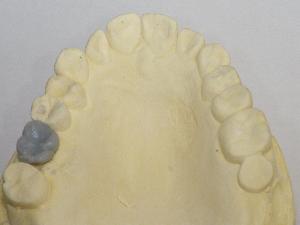

STEP6 上部構造の設置

STEP7 上部構造のチェック